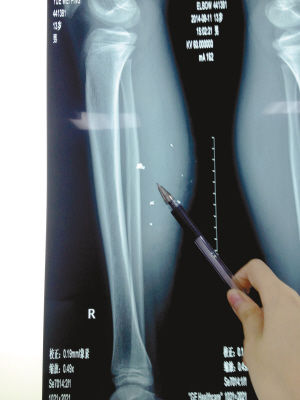

X光片顯示:手機(jī)電池內(nèi)的物質(zhì)被炸進(jìn)了小平的右小腿里

8月10日凌晨,小平轉(zhuǎn)院至重慶醫(yī)科大學(xué)附屬兒童醫(yī)院。小平的主治醫(yī)生骨科二病房周悅航醫(yī)生介紹,入院時(shí)小平右小腿腫脹,經(jīng)檢查,發(fā)現(xiàn)有爆炸傷伴異物殘留。傷口較深,約1.5厘米~2厘米,手機(jī)爆炸后進(jìn)入患兒小腿的異物約有10處。周悅航說,由于進(jìn)入皮膚的異物較多,已深入肌肉,且比較分散,最深的一塊貼近骨頭,可能需要多次手術(shù)。

另外,醫(yī)生擔(dān)心手機(jī)爆炸后金屬物進(jìn)入患兒體內(nèi)可能會對患兒肌肉造成損傷,所以需盡快手術(shù)。據(jù)悉,8月14日上午,小平將接受小腿爆炸傷清創(chuàng)與異物取出術(shù)。